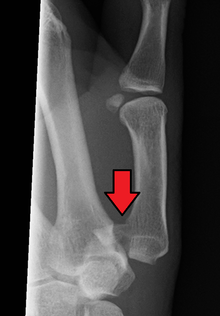

Bennett fracture on x-ray

Bennett fracture is a fracture of the base of the first metacarpal bone which extends into the carpometacarpal (CMC) joint.[1] This intra-articular fracture is the most common type of fracture of the thumb, and is nearly always accompanied by some degree of subluxation or frank dislocation of the carpometacarpal joint.

In the case of the Bennett fracture, the proximal metacarpal fragment remains attached to the anterior oblique ligament, which in turn is attached to the tubercle of the trapezium bone of the CMC joint. This ligamentous attachment ensures that the proximal fragment remains in its correct anatomical position.

The distal fragment of the first metacarpal bone possesses the majority of the articular surface of the first CMC joint. Unlike the proximal fracture fragment, strong ligaments and muscle tendons of the hand tend to pull this fragment out of its correct anatomical position.